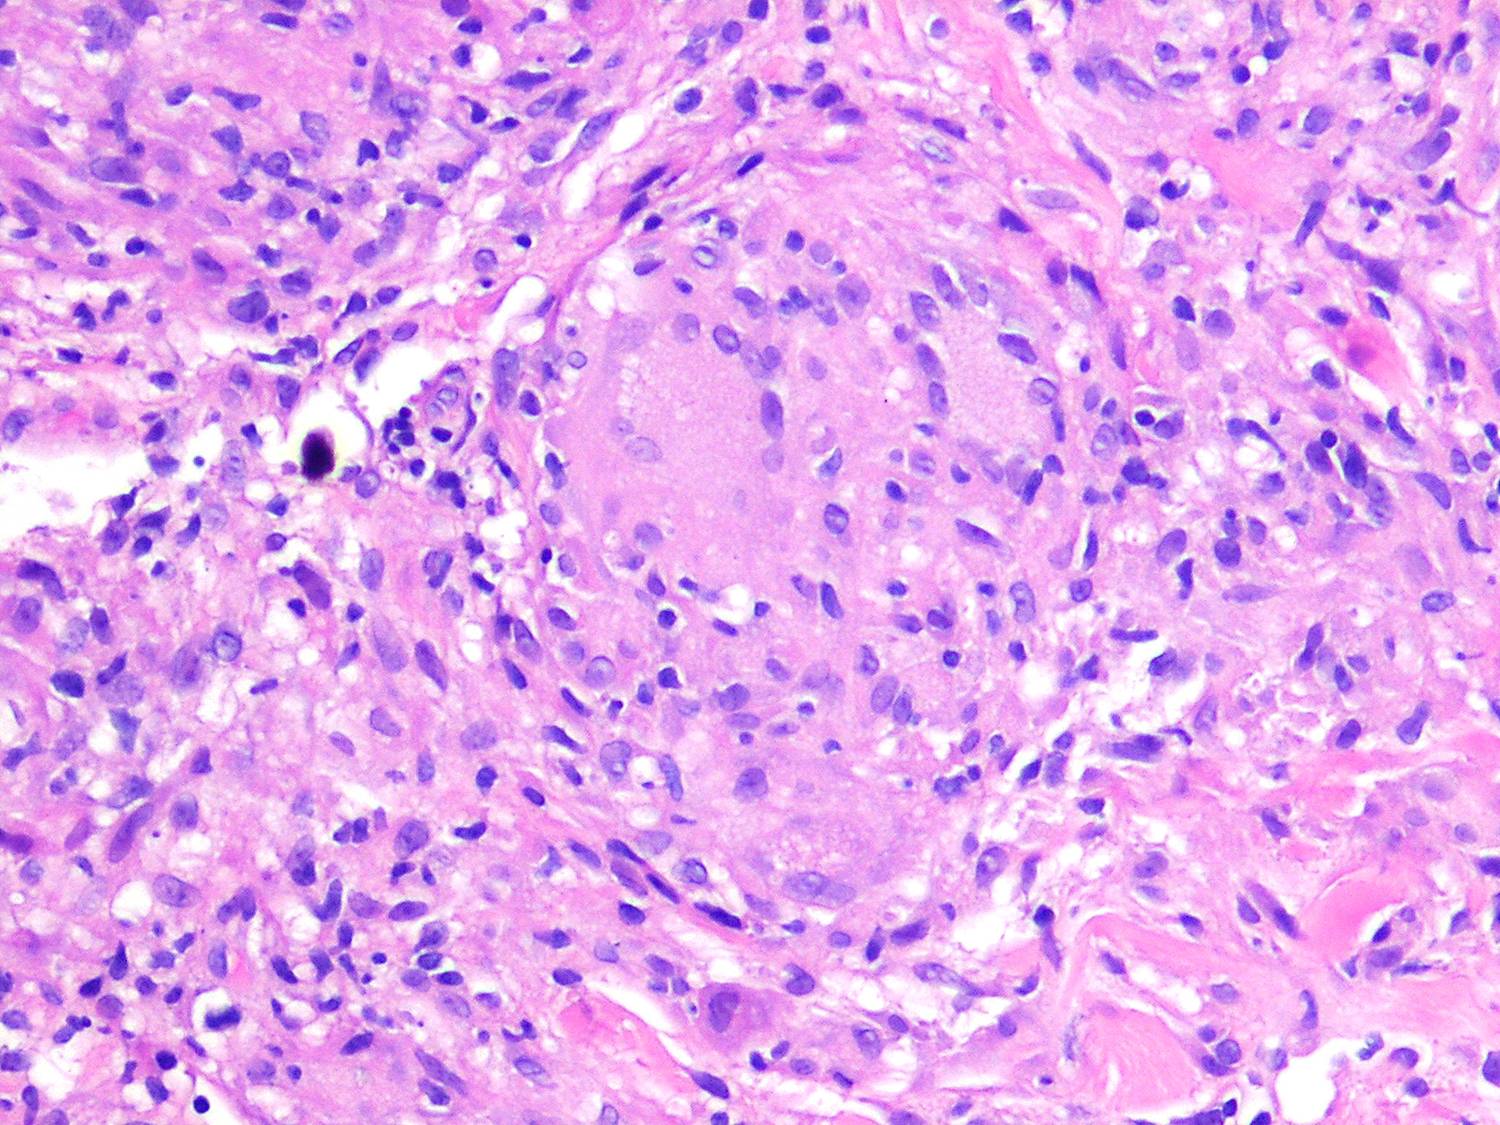

Like lesions in other organs, the cutaneous lesions of chronic, persistent sarcoidosis are characterized by the presence of circumscribed collections of epithelioid histiocytes-so-called epithelioid cell tubercles-which show little or no necrosis .

The papules, plaques, and lupus pernio-type lesions show variously sized aggregates of epithelioid cells scattered irregularly through the dermis with occasional extension into the subcutis (. In the erythrodermic form, the infiltrate shows small granulomas in the upper dermis intermingled with numerous lymphocytes

and, rarely, also giant cells . Typical sarcoidal granulomas are found in the ichthyosiform lesions , in ulcerated areas , and in atrophic lesions . Verrucous sarcoid exhibits prominent associated acanthosis and hyperkeratosis . Biopsies of

In typical cutaneous lesions of sarcoidosis, the well-demarcated islands of epithelioid cells contain few, if any, giant cells. Those that are present are usually of the Langhans type. A moderate number of giant cells can be found in old lesions. These giant cells may be large and irregular in shape. In a minority of cases, giant cells contain asteroid bodies or Schaumann bodies . Asteroid bodies , which are more common, are star-shaped eosinophilic structures that, when stained with phosphotungstic acid-hematoxylin, produce a center that is brown-red with radiating blue spikes . Schaumann bodies are round or oval, laminated, and calcified, especially at their periphery. They stain dark blue because of the presence of calcium. Neither of these two bodies is specific for sarcoidosis: They have been observed in a variety of other granulomas, including those of leprosy, tuberculosis, foreign-body reactions, and necrobiotic xanthogranuloma .

Classically, sarcoid has been associated with only a sparse lymphocytic infiltrate, particularly at the margins of the epithelioid cell granulomas . Because of the scarcity of lymphocytes, the granulomas have been referred to as “naked” tubercles. However, lymphocytic infiltrates in sarcoid may occasionally be dense, as in tuberculosis . Occasionally, small foci of fibrin or necrosis showing

eosinophilic staining is found in the center of some of the granulomas . A reticulum stain of sarcoid reveals a network of reticulum fibers surrounding and permeating the epithelioid cell granulomas. If the granulomas of sarcoidosis involute, fibrosis extends from the periphery toward the center, with gradual disappearance of the epithelioid cells . Fibrosis, however, is minimal to absent in most examples of sarcoidosis, with the exception of the morpheaform variant, where it is prominent {191}. Other features that may sometimes be seen include elastophagocytosis, increased dermal mucin, and lichenoid inflammation .